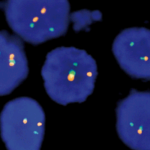

Quick Order Quick Order Name Email Address Company Address Catalog Number Quantity Message 14 + 5 = Submit Category Blocking Reagents Both Counterstain Country International US Detection Kit Detection Kit Detection kit 1-Step Polymer Kit Detection Kits - IHC 1-Step Polymer HRP Kits IHC AP Detection Kit IHC HRP Detection Kit IHC Mouse on Mouse 1-step Poly HRP kit New & Improved 1-Step Polymer HRP Kit IHC New & Improved Polymer HRP Kits IHC Polymer HRP Kits IHC Rapid Polymer HRP Kits IHC Double Staining eFISH Detection Kits ISH-Detection Kits Multiplex Detection Kits New & Improved Detection Kits Polymer HRP Kits IHC eFISH Enzymes for Tissue Processing Enzymes for Tissue Processing i6000 and Manual Instruments ISH Probes ISH-Detection Systems Links / Labels items-Manual Microscope Microchamber Slides & Coverslips for Xmatrx Microscope Slides & Accesories for i6000 and Manual Microscope Slides & Accessories Microscope Slides & Accessories miRNA Probes Primary Antibodies A Antibody Cocktail B C D E F G H I J K L M N O P R S T U V W Y Z Reagents Antigen Retrieval Solutions Blocking Reagents Blocking Reagents Buffers and Diluents Buffers eFSH Buffers ISH Buffers Counter Stains Detection Kit Dewaxing & Rehydration Reagents Diagnostic Antigen Retrieval Solutions eFISH Antigen Retrieval Solutions ISH Blocking Reagents ISH Enzymes Mounting Media eFISH Mount Media Nucleic Acid Retrieval Substrates & Chromogens ISH DAB replacements Slide Labels Vials Immunohistochemistry In situ Hybridization eFISH eFISH Probes eFISH Visualization Kits eFISH Visualization Kit Cyto eFISH Visualization Kit Histo Visualization Kit Ancillaries & Consumables Consumable Kits IHC Consumable Kits ISH Consumable Kits Counterstain and Mounting Media Counterstain Mounting PAP Pen Pipette Tips Reagent Vials & Accessories Reagent Vials & Accessories for i6000TM Diagnostics Reagent Vials & Accessories for Open system Automation Reagent Vials & Accessories for Xmatrx Elite Reagnet vials and accessories-1 Automation Detection Systems miRNA ISH Multiplexing & Double Staining Filters Sort results Reset Apply eFISH ETV6 Dual Color Break Apart Probe Select 10 tests (RTU)20 tests (RTU) Buy here eFISH ETV6 Dual Color Break Apart Probe Select 10 tests (RTU)20 tests (RTU) Buy here eFISH ETV6/RUNX1 Dual Color Dual Fusion Probe Select 10 tests (RTU)20 tests (RTU) Buy here eFISH ETV6/RUNX1 Dual Color Dual Fusion Probe Select 10 tests (RTU)20 tests (RTU) Buy here eFISH EWSR1 Dual Color Break Apart Probe Select 10 tests (RTU)20 tests (RTU) Buy here eFISH EWSR1 Dual Color Break Apart Probe Select 10 tests (RTU)20 tests (RTU) Buy here eFISH FGFR1/CEN 8 Dual Color Probe Select 10 tests (RTU)20 tests (RTU) Buy here eFISH FGFR1/CEN 8 Dual Color Probe Select 10 tests (RTU)20 tests (RTU) Buy here eFISH FGFR2/CEN 10 Dual Color Probe Select 10 tests (RTU)20 tests (RTU) Buy here eFISH FGFR2/CEN 10 Dual Color Probe Select 10 tests (RTU)20 tests (RTU) Buy here ‹ 1 … 83 84 85 … 146 ›